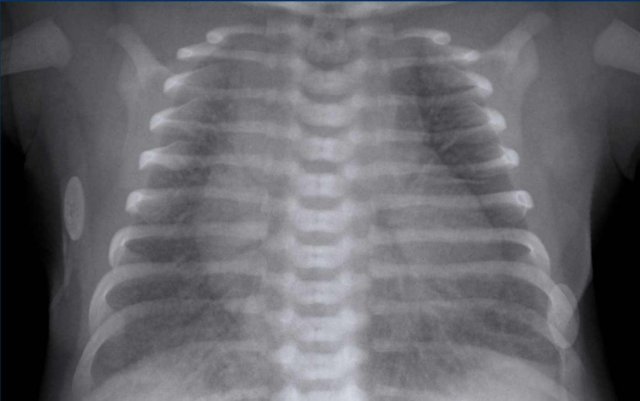

One day old neonate, 27 weeks of gestational age.

Granular opacification of both lungs.

Vessels and cardiac silhouette are well depicted.

Conclusion: RDS grade 1.

Peripherally inserted central catheter (PICC) line, curled in the right atrium.  The PICC should be pulled back to the level of the superior vena cava and right atrium.